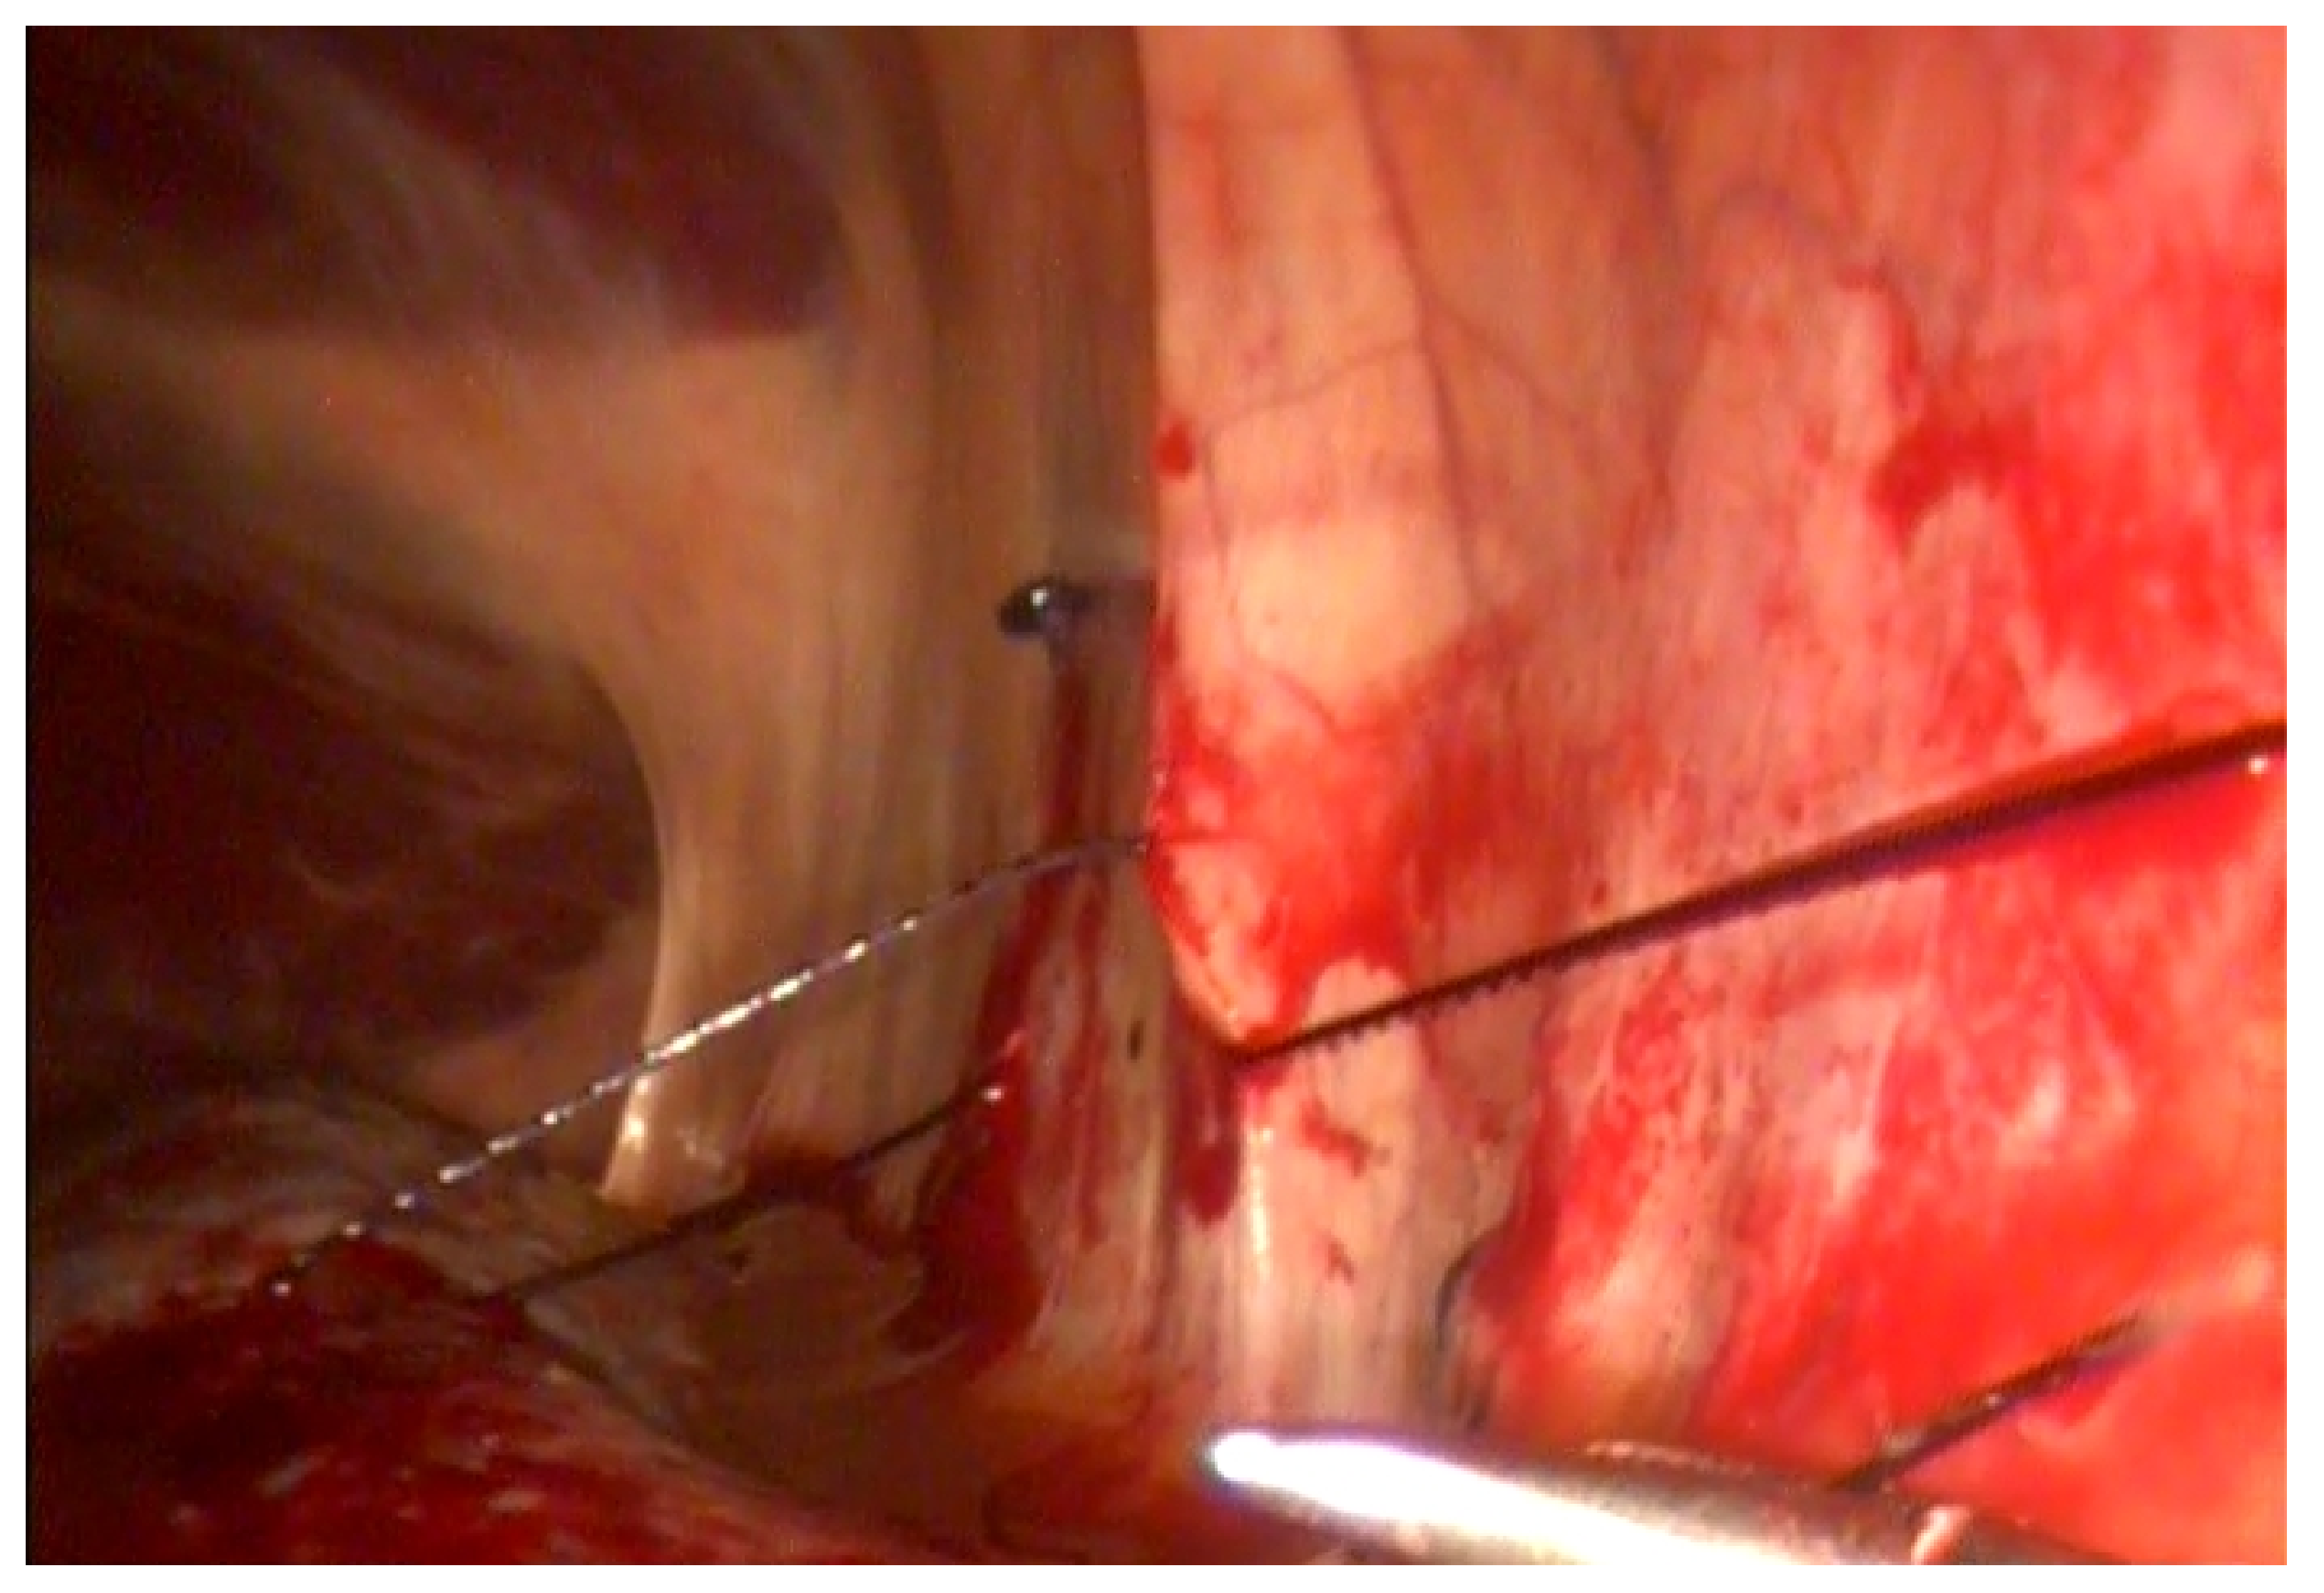

To obliterate the NSS, a continuous suture was used with a 30-mm-long, one-half-circle taper needle attached to loop-ended, USP 0 absorbable polydioxanone knotless suture material (V-Loc 90, Covidien Italia S.p.A., Segrate, Milano, Italy, as previously described or with a 26-mm-long, one-half circle taper needle attached to USP 2 absorbable polydioxanone self-retaining barbed suture with a PDO button in the end (Filbloc®Assut Europe S.p.a., Magliano dei Marsi, L’Aquila, Italy). The closure of the NSS occurs through the apposition of the suture between the perirenal fascia and the dorso-medial aspect of the fibrous capsule of the spleen in a cranio-caudal orientation [6]. The first step of the suture is performed in the most cranial part of the ligament, with the dorso-ventral direction of the needle. The needle passes at the same height on the spleen capsule with ventro-dorsal direction. The barbed suture, after the first passage, is self-retained. The simple continuous suture is continued at intervals of about 1.5 cm to obliterate the space (Figure 1). To end the suture, two additional backwards passages were performed. When the suture is finished, laparoscopic scissors are used to cut the thread.

Figure 1. NSS ablation with barbed suture (Filbloc®). Note the button at the end of the thread that facilitates application of the first bite.